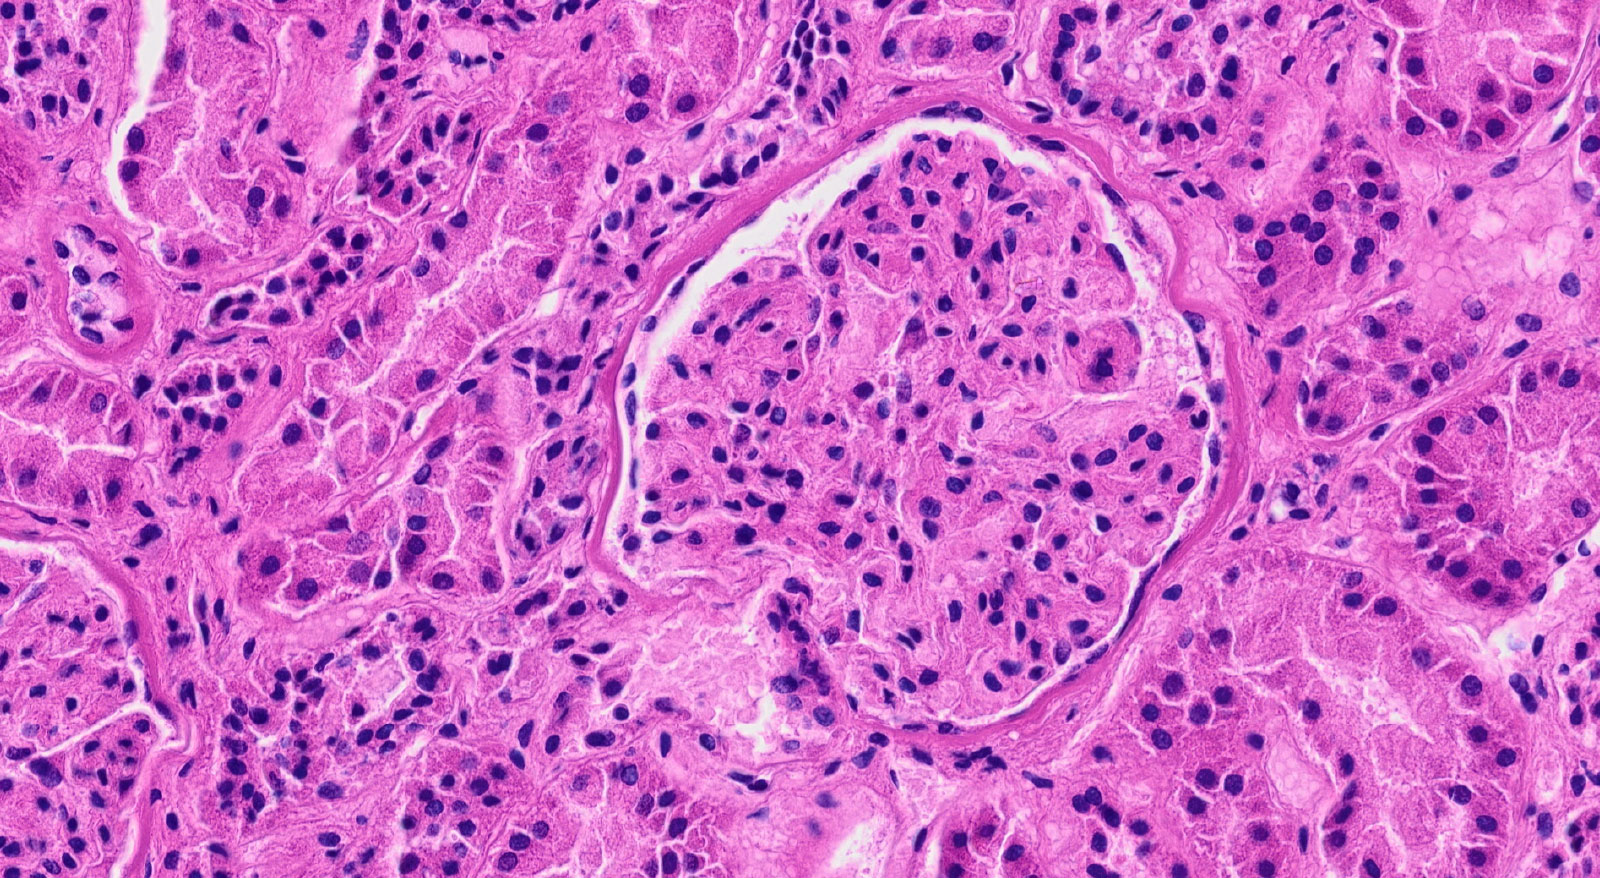

病理組織の標本。HE染色が施されており、細胞核が青紫色に、細胞質や細胞外基質がピンク色に染まっています。

現在の病理診断は、病理標本を染色し、その組織の構造を観察することで診断します。しかし、病理組織の構造は、疾患やがんの種類によって大きく異なり、臓器ごとの専門医がいるほど高度な知識と経験を必要とします。たとえば、HE染色した細胞核が濃く染まる「濃染」という現象は重要な病理所見の一つですが、その“濃さの程度”を客観的に定量化するのは難しく、診断は病理医の経験に依存する部分があります。これに対して、がんなどの異常組織は正常組織と比べて組織の状態が異なるため、染色液の入り具合が変化し、組織を通る光の状況も変わるのではないかというのが私の見解です。従来の組織構造情報に、組織を透過する光という物理的な量を加えることで、より高精度な解析が可能になるのではないかと考えています。